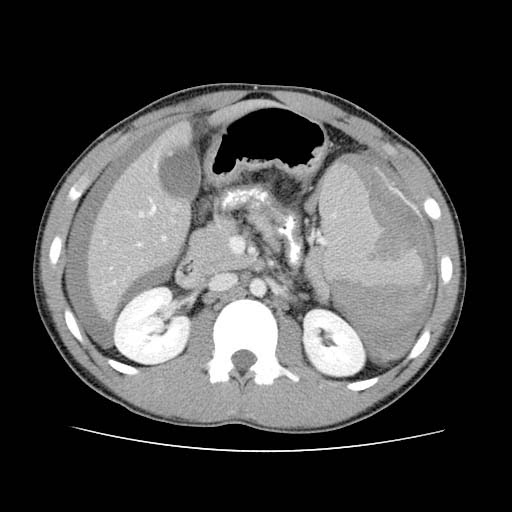

The CT scan shows a high grade splenic laceration with a “contrast

blush” within the splenic parenchyma.

Hemoperitoneum (thick grey outline surrounding both liver and spleen)

Contrast Blush (blue arrow)

Two

radiologic features that are searched for on the initial abdominal CT scan are

the presence of active hemorrhage

(extravasation) or an intraparenchymal

vascular injury referred to as a “contrast

blush.” (Both are seen in the images above.)